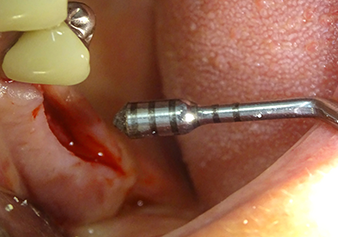

Dopo un controllo intermedio (Fig. 4) è stata eseguita un'ulteriore fase di preparazione (Fig. 5). Lo strumento idraulico Z35P è stato utilizzato in un secondo momento per sollevare la membrana sino alla posizione desiderata (Fig. 6 e 7). In seguito alla suddetta operazione, si è proceduto ad una ulteriore preparazione piezochirurgica della sede dell'impianto conclusasi con l'applicazione della fresa e della fresa a spallamento sul diametro dell'impianto di 4,8 mm. Il materiale di rinforzo (dimensione delle particelle di ca. 0,8 - 1,6 mm) è stato introdotto sotto la membrana di Schneider prima che venisse inserito l'impianto (Fig. 8).